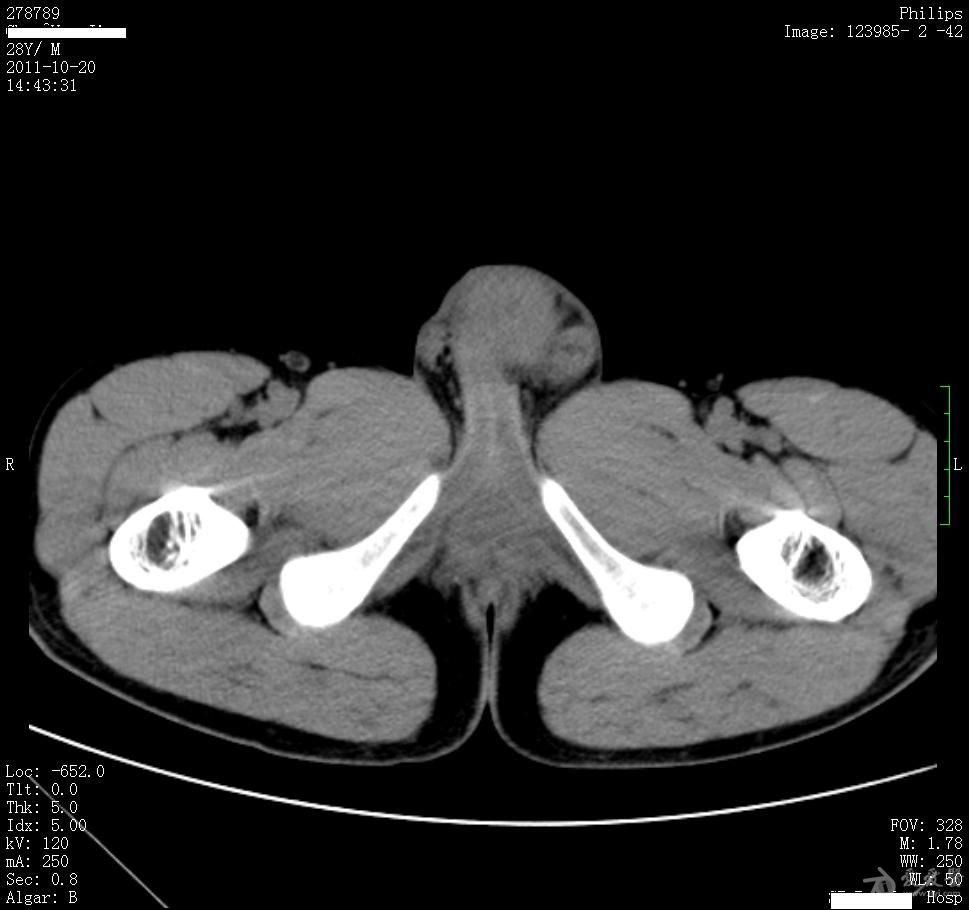

病例15睾丸肿大5月余结果在6楼

图片尺寸969x910